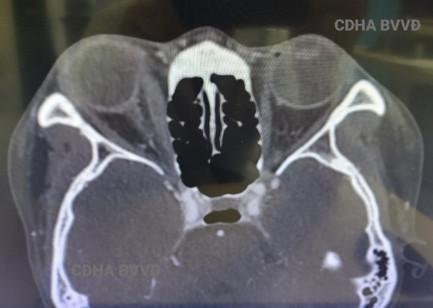

| Mắt phải sưng nề bầm tím, gần như mù toàn bộ, thị lực chỉ còn sáng tối (+) và hình ảnh phù nề võng mạc và khu cơ vận nhãn trong mắt phải trên chụp CT của bệnh nhân. |

PGS.TS Nguyễn Hồng Hà - Trưởng khoa Phẫu thuật Tạo hình Thẩm mỹ, Bệnh viện Việt Đức cho biết, người bệnh đến viện trong tình trạng mắt phải phù nề căng tím đỏ, thị lực gần như mất hoàn toàn, chỉ còn phân biệt được sáng tối 1 cách khó khăn, sụp mi rõ, cơ vận nhãn trong liệt hoàn toàn.

"Kết quả hình ảnh cho thấy võng mạc bệnh nhân phù nề gấp 2 3 lần bình thường, khối cơ vận nhãn trong và tổ chức mỡ cạnh nhãn cầu có dấu hiệu thiếu máu, phù nề nguy cơ hoại tử toàn bộ. Lưu lượng máu động mạch đến ổ mắt mắt bên phải giảm rất nhiều so với bên lành"- PGS.TS Nguyễn Hồng Hà thông tin.